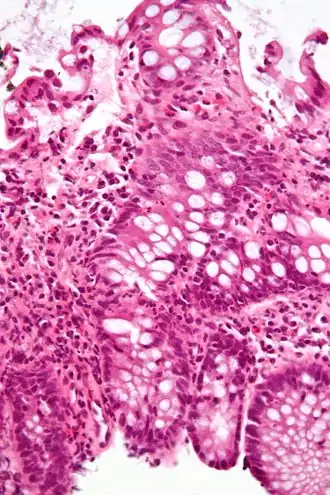

Micrografía que muestra inflamación del intestino grueso en un caso de enfermedad inflamatoria intestinal. Biopsia colonica. Tinción hematoxilina-eosina.